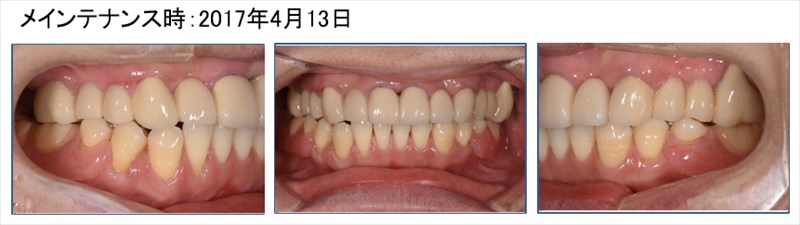

この症例は前歯の揺れを主訴に来た患者さま

奥歯もなく咬めないとおっしゃっていました。

術前のレントゲンでは根尖病変(根の先に膿が溜まっている状態)が確認され、そこに垂直的な骨欠損があり7mmのポケットがありました。右のレントゲンを見て頂くと骨が再生しポケットは2mmに。根尖病変(根の先に膿が溜まっている状態)も改善されています。この症例は歯周病の再生療法と精密根管治療どちらのクオリティーが落ちても上手くいかない症例です。

勿論全体的に歯周病や虫歯も治り良く食べられるとおっしゃって頂けました。